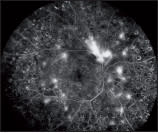

Non-contact ultra-widefield imaging is designed with a wide field of view to enhance recognition of the extent of such conditions as retinal vein occlusion, diabetic retinopathy, and retinal tumors and cancers (Figure 1).

Figure 1. Fluorescein angiography of diabetic retinopathy obtained with the Spectralis Non-Contact Ultra-Widefield imaging. The moveable camera head of the Spectralis further extends the reach out into the far periphery.

COURTESY: HEIDELBERG ENGINEERING